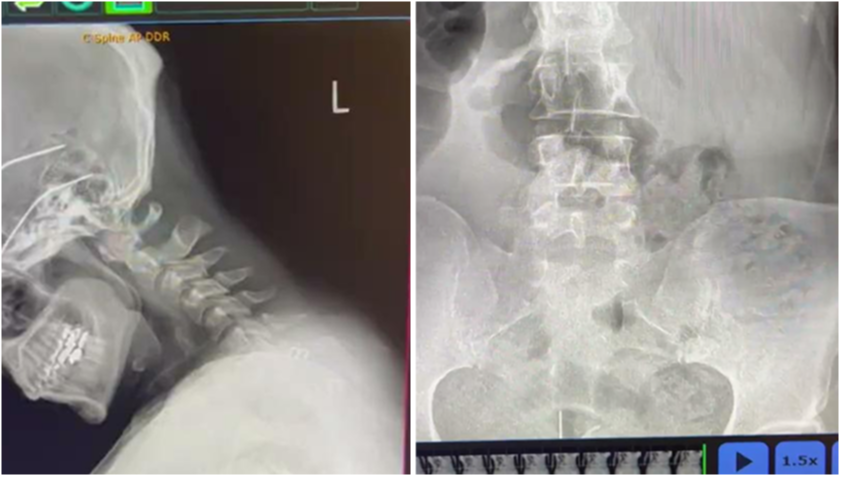

2. STRUCTURAL X-RAY

PRS utilizes static X-ray imaging as a critical foundation for precise chiropractic care. This essential tool helps rule out pathologies, ensuring a safe and informed approach to treatment.

By providing a clear baseline for further diagnosis and care, static X-rays enable chiropractors to develop targeted strategies tailored to each patient’s needs.

Serving as the cornerstone for our more advanced technologies and techniques, this method ensures a solid starting point, empowering practitioners to build upon accurate data for optimal spinal correction and lasting patient outcomes.

3. PULSE X-RAY DIGITAL MOTION

You'll be introduced to the tool that has revolutionized chiropractic care. These "moving" x-rays have proven to be over 98% accurate - compared with the 10-20& accuracy rates from palpation.

Pulse X-Ray Example #1